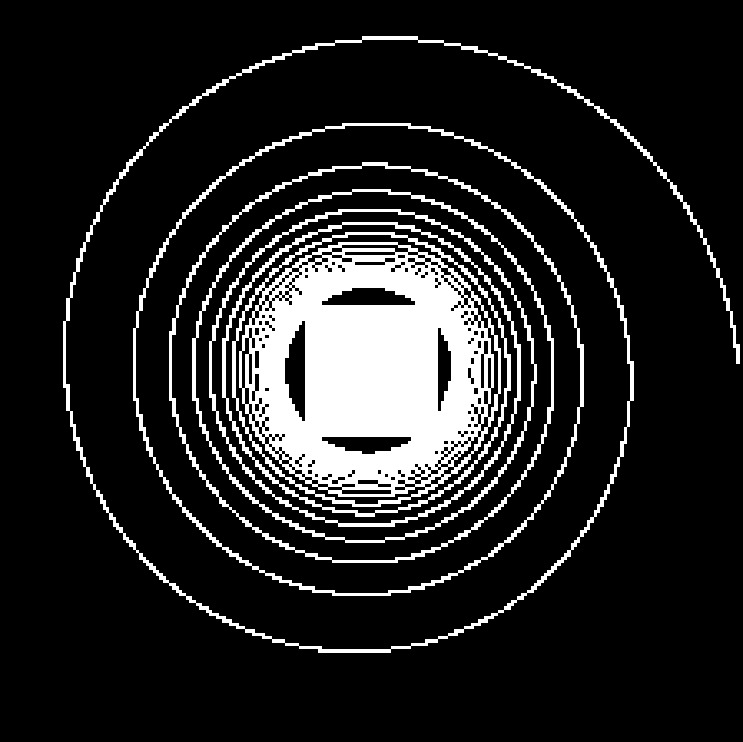

Compressed Sensing (CS) provides a theoretical framework to justify the downsampling of -space (2D or 3D Fourier domain) in Magnetic Resonance Imaging (MRI). CS-MRI is usually based on independent random drawing of -space locations according to a prescribed density. From recent theoretical works [3, 4], one can derive an optimal sampling density that reduces at most the number of samples collected in MRI without degrading the image quality at the reconstruction step [5, 6]. In [7], simulations show that distributions with radial decay (see Fig. 1(a)) with full -space center acquisition perform better in numerical experiments.

However, such sampling schemes are not performed along continuous lines and thus not physically plausible in MRI because of the constraints involved on the magnetic field gradient (magnitude and slew-rate). In [8], we have proposed a new approach to design continuous sampling trajectories based on the solution of Travelling Salesman Problem (TSP), as illustrated in Fig. 1(b). The specificity of this approach is that the empirical distribution of the trajectory can approximate any prescribed distribution . Such a curve is called a -Variable Density Sampler (-VDS). Unfortunately, continuity of the sampling trajectory is not a sufficient condition in MRI and it is not clear how to design admissible gradient waveforms to traverse such a trajectory.

| (a) | (b) |

|---|---|

|

|